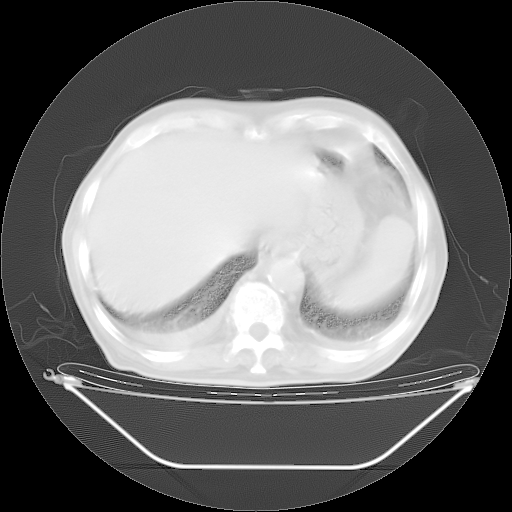

今天复查肺部CT,发现双肺广泛磨玻璃样改变。所以我把3月19日和5月9日相隔50天的肺部CT上传。请大家会诊。

2009年3月19日肺部CT片。

5月9日肺部CT(在4月27日齐鲁医院肺部CT描述部分肺组织磨玻璃样改变,12天后肺组织广泛磨玻璃样改变)

大致读了系列胸部CT:纵隔窗无明显异常,肺窗:从4、27至今:主要是双肺中下野外带可见毛玻璃样改变,目前处于急性肺泡炎阶段,至于原因考虑1、结替组织或胶原血管性疾病所致?2、恶性疾病如恶组在肺部所致的表现或细支气管肺泡癌?3、药物或其它原因如肺蛋白沉着症所致肺泡炎目前不太可能?总之,明天就去请我院的呼吸科、感染科、血液科和临免专家会诊哈。